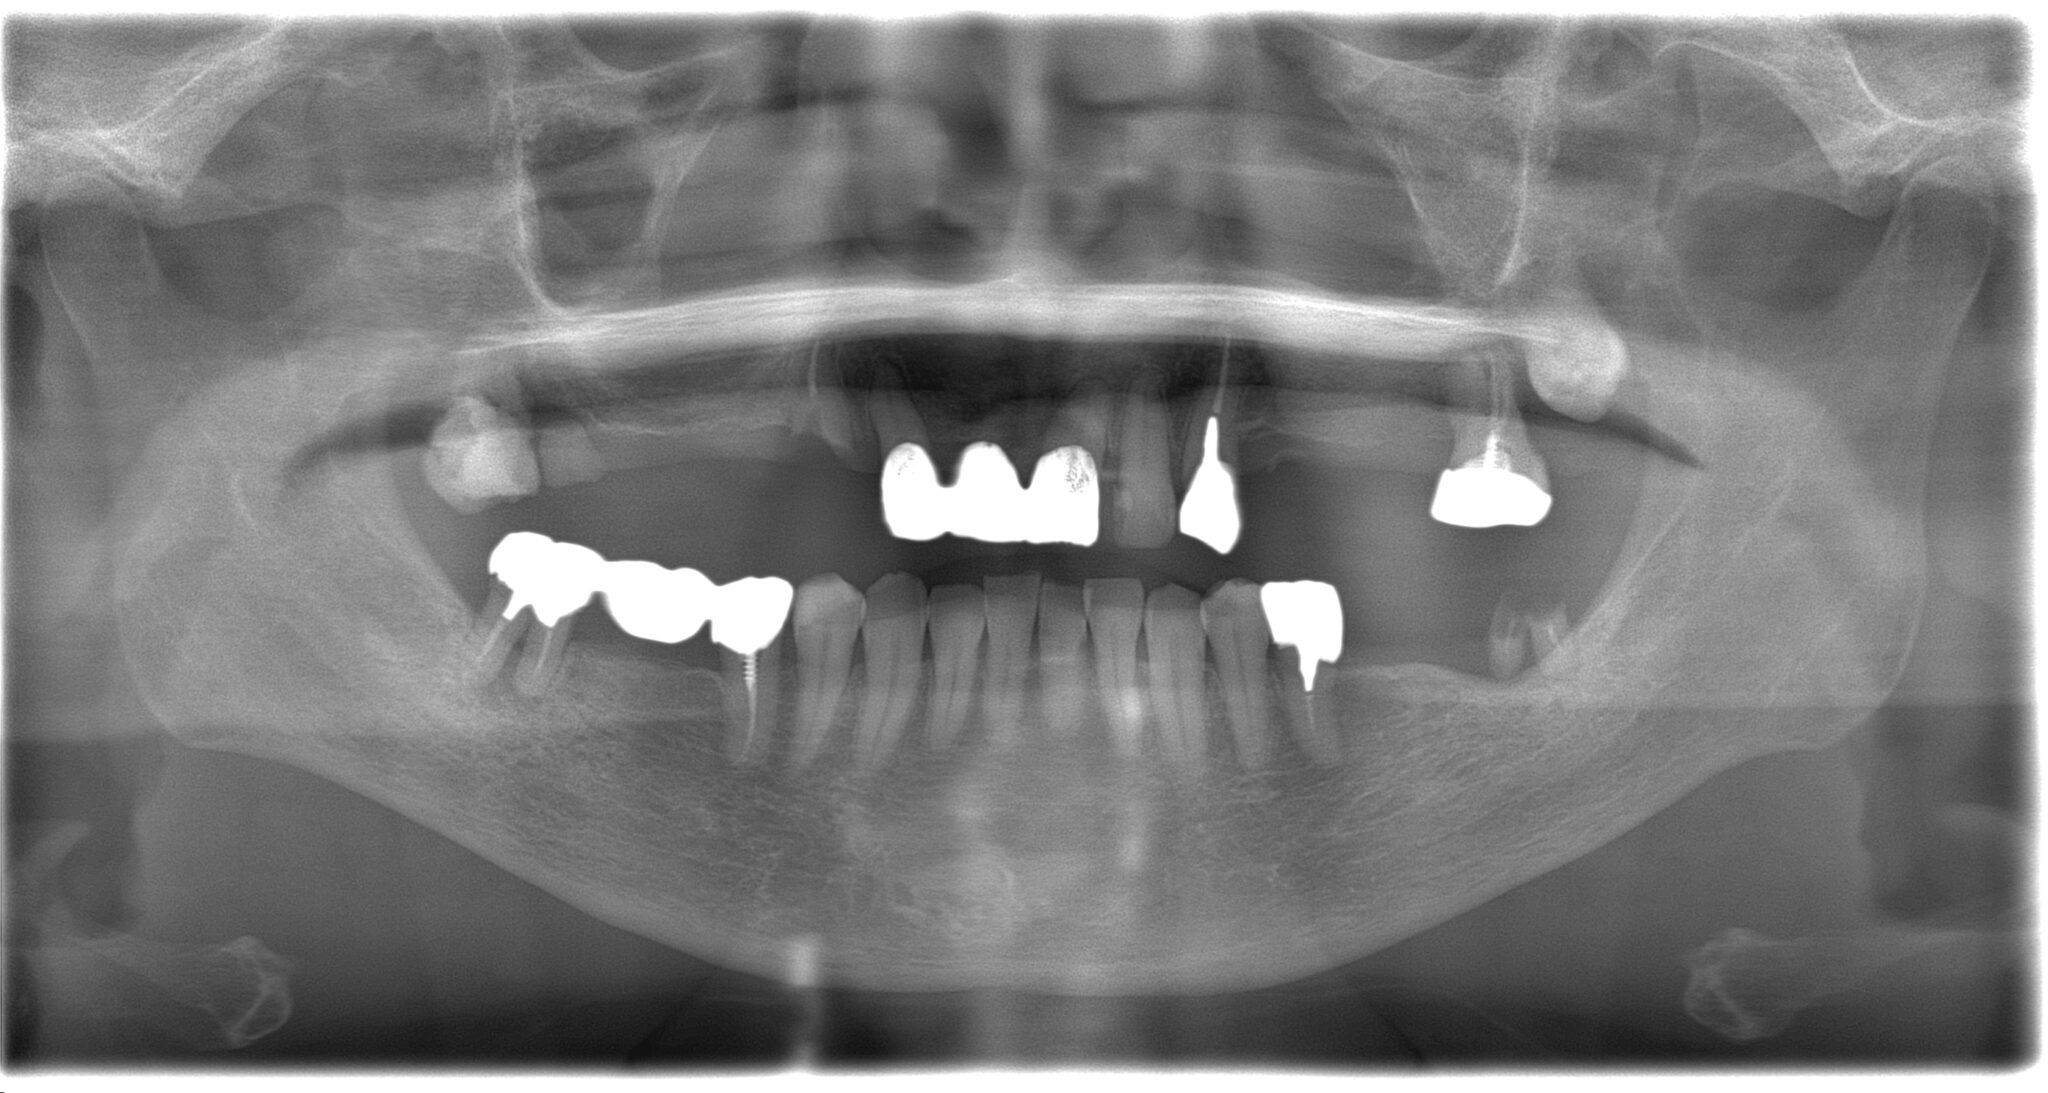

全顎治療症例

| 診断名・ 主な症状 |

臼歯部欠損 |

| 治療内容 | インプラント埋入(右上4・6,左上4・6,右下6,左下6) ジルコニアBr(右上3―左上3) ジルコニア(右下5,左下5) |

インプラント 1年5ヶ月/13回 ジルコニアBr、ジルコニアクラウン 3ヶ月/10回 |

| 費用 | インプラント: 2,552,000円 その他治療: 640,000円 合計 3,192,000円 *いずれも税込 |